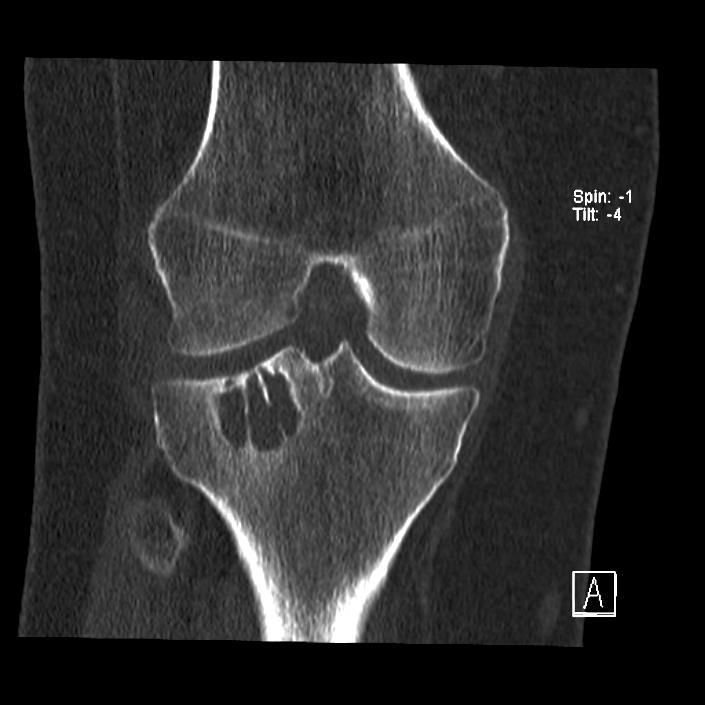

Op de SEH kwam een 40-jarige man met een pijnlijke rechter knie nadat hij zich had verstapt. Bij lichamelijk onderzoek viel een pijnlijke zwelling op, die berustte op lokaal oedeem ten gevolge van het ongeval. Ook was er sprake van drukpijn over de laterale zijde van het femur. Flexie in het kniegewricht was beperkt tot maximaal 70 graden. De collaterale ligamenten en de kruisbanden waren intact. Op de röntgenopnamen werd bij toeval een opheldering gezien in het laterale deel van de proximale tibia, waarna een CT-scan werd verricht.